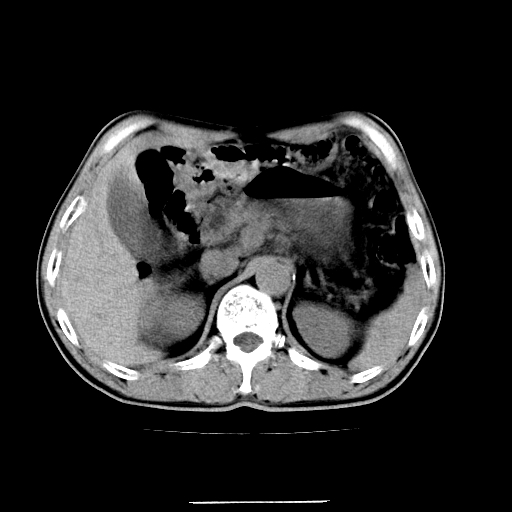

患者男,64岁,胃癌术后三个月,无明显不适。请讨论一下胰头前方小圆形低密度影为淋巴结还是肠管?

增强第6幅图上有气液平相通,是肠管,右肾低密度灶形态不规则似有壁结节,不除外转移.

应该考虑是肠管,理由1、平扫和增强对比,形态和内部的密度有明显改变。2、增强图片可见明显气液平面。

是肠管影,肠壁有强化。

一个形态变化大应该是肠管。

另一个上下观察不成形,强化也不符合淋巴结表现故考虑术后改变。

另外,胰腺体部密度在平扫和增强时均不太均匀,似有数个小的囊状低密度区存在。不知道增强时其他期如何?应该高度警惕为转移性病变。

胰头右侧低密度影卡考虑为肠管;胰头前部低密度影,增强环形强化,结合临床首先考虑转移灶,其次考虑淋巴结结核(中心干酪性坏死)。